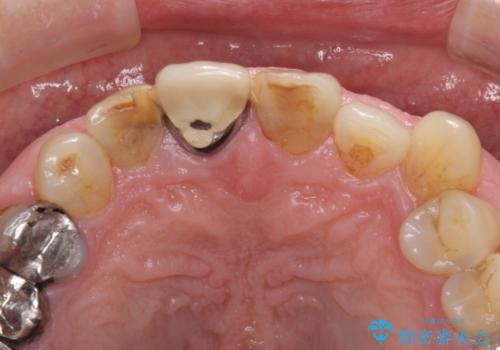

- 前歯がぐらつくことを主訴にご来院された患者様です。ご本人は抜歯と考えており、インプラント以外の治療をご希望でした。しかしながらぐらついていた原因は、古い差し歯が取れかけていたことでした。

遠方から通院されること、仕事上短期間で治療したいとのことを考慮して、残っている歯はかなり小さいものの、保存すべきと判断して当日処置から行いました。

残っている歯が小さいと、差し歯はぐらつきやすくなりますが、その形態によっては抜歯を回避できることがあります。

根管治療について

保険根管治療は回数がかかることが多く、終了予定がわかりにくいです。

当院では、根管治療は長い時間のご予約を頂き、多くの場合2~3回で終わります。

根管治療は歯内の治療なので患者様には見えない場所ですが、ここが細菌で汚染されると激しい痛みや長引く違和感の原因になります。

当院では、清潔な治療を徹底し、顕微鏡を使用した精密な治療を行っています。